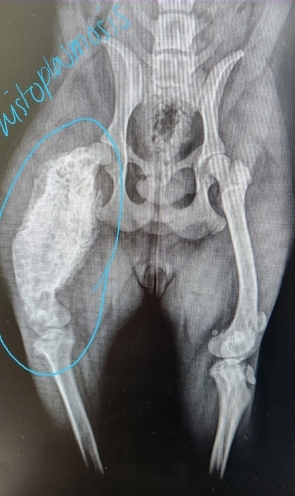

Diagnostic Imaging for Hip Dysplasia

VD most useful

Want >50% acetabular coverage!

Rads: Bone shape, remodeling, osteophytosis(neck), enthesiophytosis (Morgan’s line), laxity

Do not treat the radiograph!